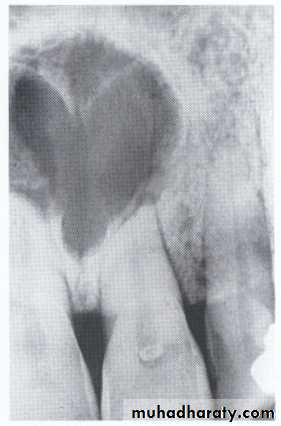

Dentigerous CystIt forms around the crown of an unerupted or supernumerary tooth at CEJ.

Some dentigerous cysts are eccentric, developing from the lateral aspect of the follicle so that they occupy an area beside the crown instead of above the crown.

It displace and resorb adjacent teeth.

It commonly displaces the associated tooth

in an apical direction.